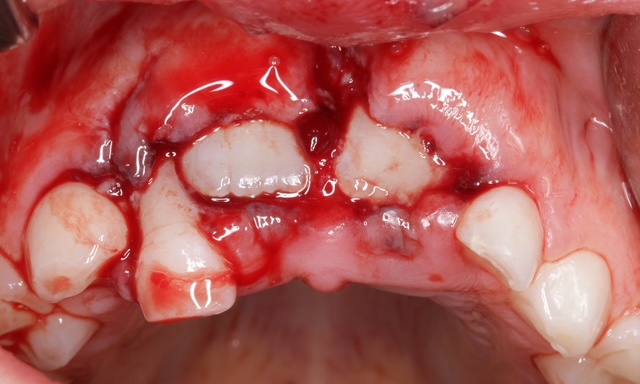

Zahntraumata zählen zu den häufigsten Notfällen in der Zahnmedizin – und sie stellen uns regelmäßig vor komplexe diagnostische und therapeutische Herausforderungen. Die Erstversorgung erfolgt in der Regel bei uns Zahnärzten in der Praxis und ist entscheidend für den Therapieverlauf. Fehler können lebenslange Folgen für unsere Patienten haben. Umso wichtiger ist es, dass jede Praxis über aktuelles Wissen und Handlungssicherheit verfügt. Professor Krastl wird uns anhand zahlreicher klinischer Fälle die aktuellen diagnostischen und therapeutischen Möglichkeiten aufzeigen. Das Seminar bietet einen fundierten Einblick in die Behandlungsstrategien des Zahnunfallzentrums Würzburg – prägnant, hochaktuell und mit direkter Relevanz für den Praxisalltag.

Diagnostik und Therapie unfallbedingter Zahnverletzungen haben in den letzten Jahren einen Wandel erfahren. Viele „traditionelle“ Therapiekonzepte sind nicht nur modernen, sondern auch wissenschaftlich abgestützten Behandlungskonzepten gewichen. Dennoch sollte die Behandlung von Zahnunfällen nicht Spezialisten vorbehalten bleiben. Das rechtzeitige Erreichen einer auf Zahnunfälle spezialisierten Einrichtung ist in den meisten Fällen völlig unrealistisch. Folglich gehört es zu den Pflichten jedes Zahnarztes, eine adäquate Diagnostik und Akutversorgung in seiner Praxis bereitzustellen, auch wenn die Routine auf diesem Gebiet fehlt. Denn falsche und nicht rechtzeitig oder nicht konsequent durchgeführte Behandlungen haben – gerade bei Kindern – oftmals weitreichende Konsequenzen, die später auch mit großem Aufwand nicht mehr kompensierbar sind.

Anhand zahlreicher klinischer Fälle werden die verschiedenen Therapiemöglichkeiten nach Zahntrauma demonstriert und die aktuellen Guidelines (IADT, DGZMK, DGET) diskutiert.